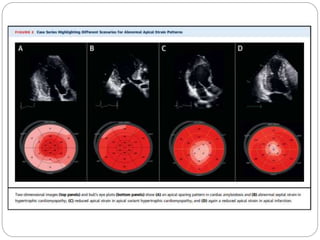

Normal Strain Displays- bulls eye

presentation

NORMAL PATTERN

DILATED

CARDIOMYOPATHY

DYSSYNCHRONY